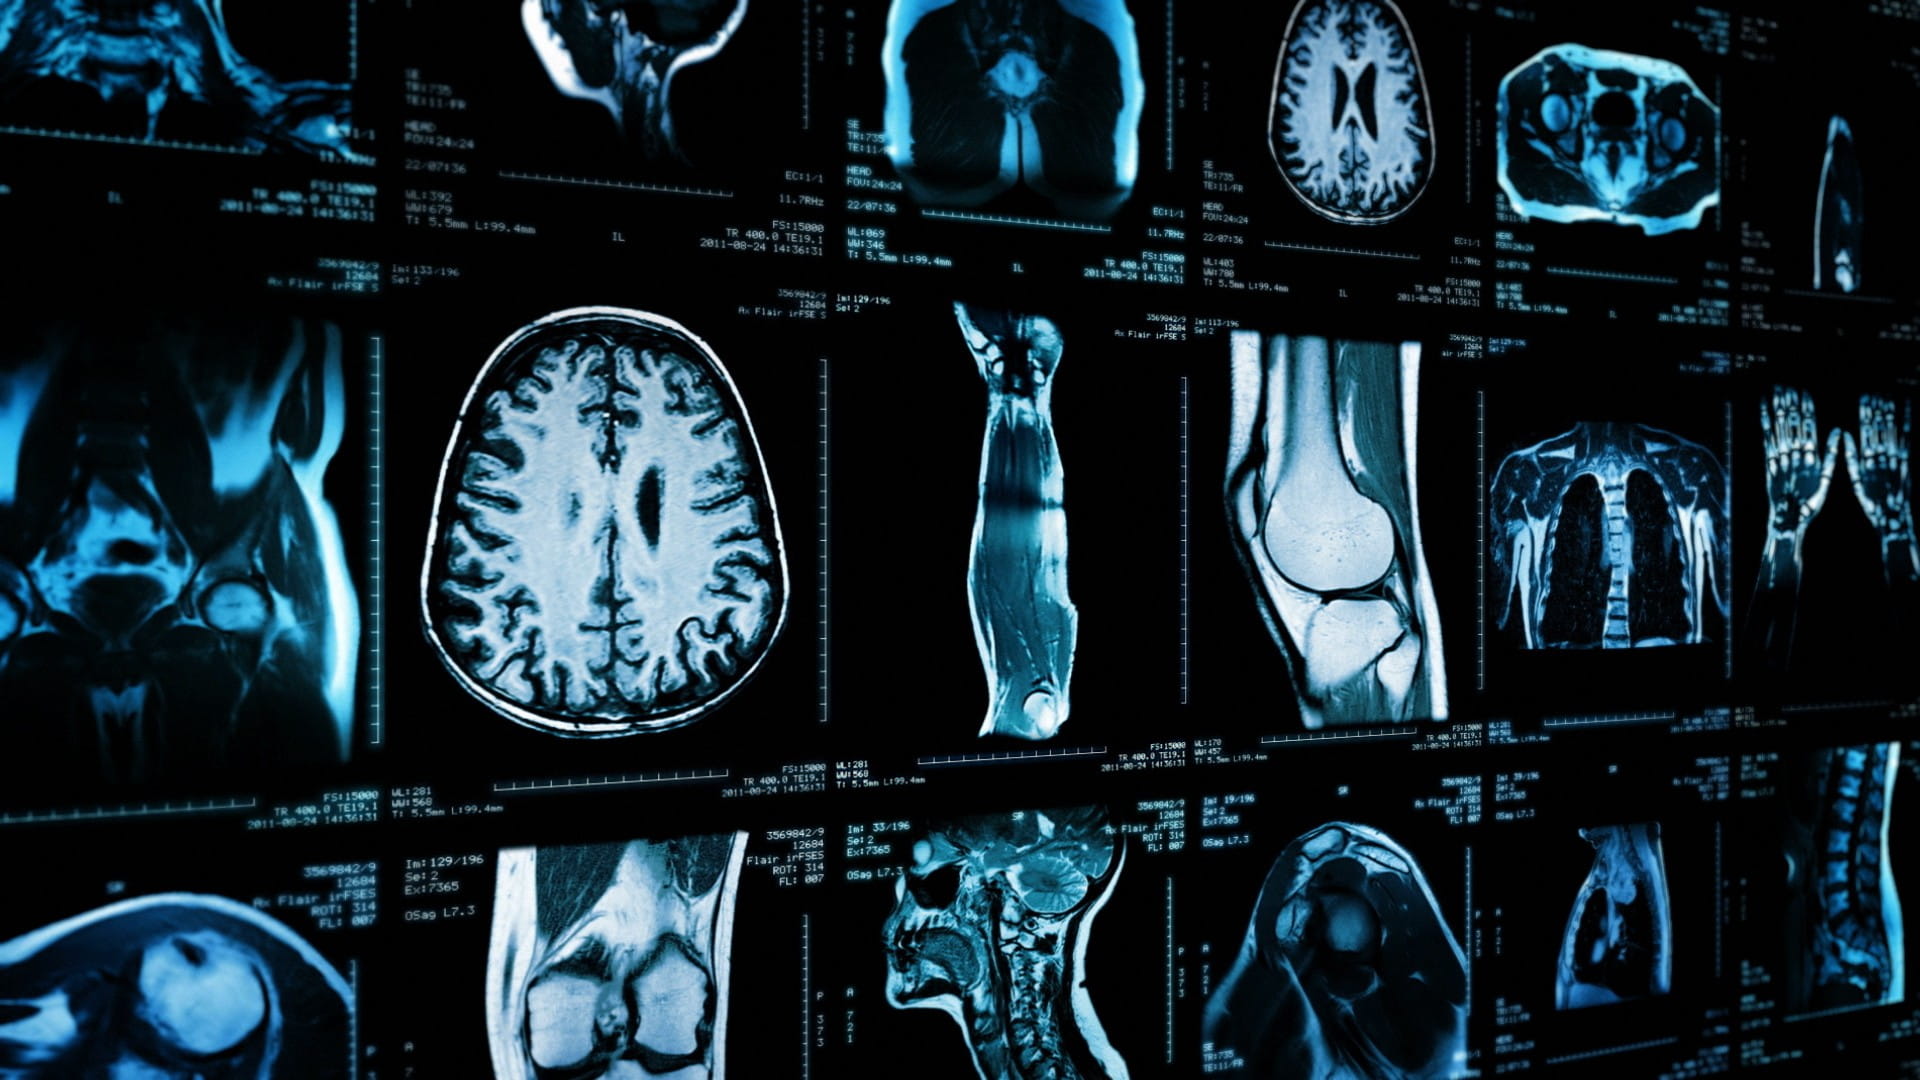

Image of a variety of different scans: skull, chest, arm, knee, etc.